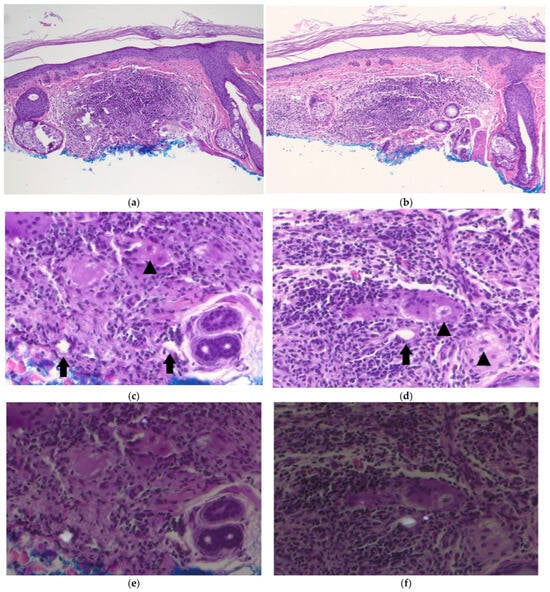

2. Case Report

3. Discussion